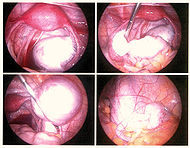

Эндометриоз

Эндометрио́з — распространённое гинекологическое заболевание, при котором клетки эндометрия (внутреннего слоя стенки матки) разрастаются за пределами этого слоя. Поскольку эндометриоидная ткань имеет рецепторы к гормонам, в ней возникают те же изменения, что и в нормальном эндометрии, проявляющиеся ежемесячными кровотечениями. Эти небольшие кровотечения приводят к воспалению в окружающих тканях и вызывают основные проявления заболевания: боль, увеличение объема органа, бесплодие. Симптомы эндометриоза зависят от расположения его очагов. Различают генитальный (в пределах половых органов — матки, яичников) и экстрагенитальный (вне половой системы — пупок, кишечник и т. д.) эндометриоз.

По распространению и глубине поражения тканей эндометриозом различают 4 стадии заболевания:

I степень — единичные поверхностные очаги.

II степень — несколько более глубоких очагов.

III степень — множество глубоких очагов эндометриоза, небольшие эндометриоидные кисты одного или обоих яичников, тонкие спайки брюшины.

IV степень — Множество глубоких очагов, большие двусторонние эндометриоидные кисты яичников, плотные сращения органов, прорастание влагалища или прямой кишки.